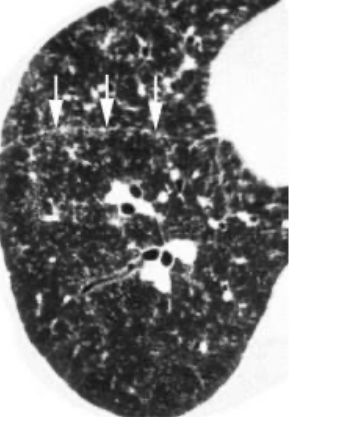

Les éléments pointés par une flèche sont ...

des plaques pleurales, apparaissant PARFOIS lors de l'exposition à l'amiante, elles ne permettent ni de poser le diagnostic ni de l'éliminer mais permettent de s'orienter